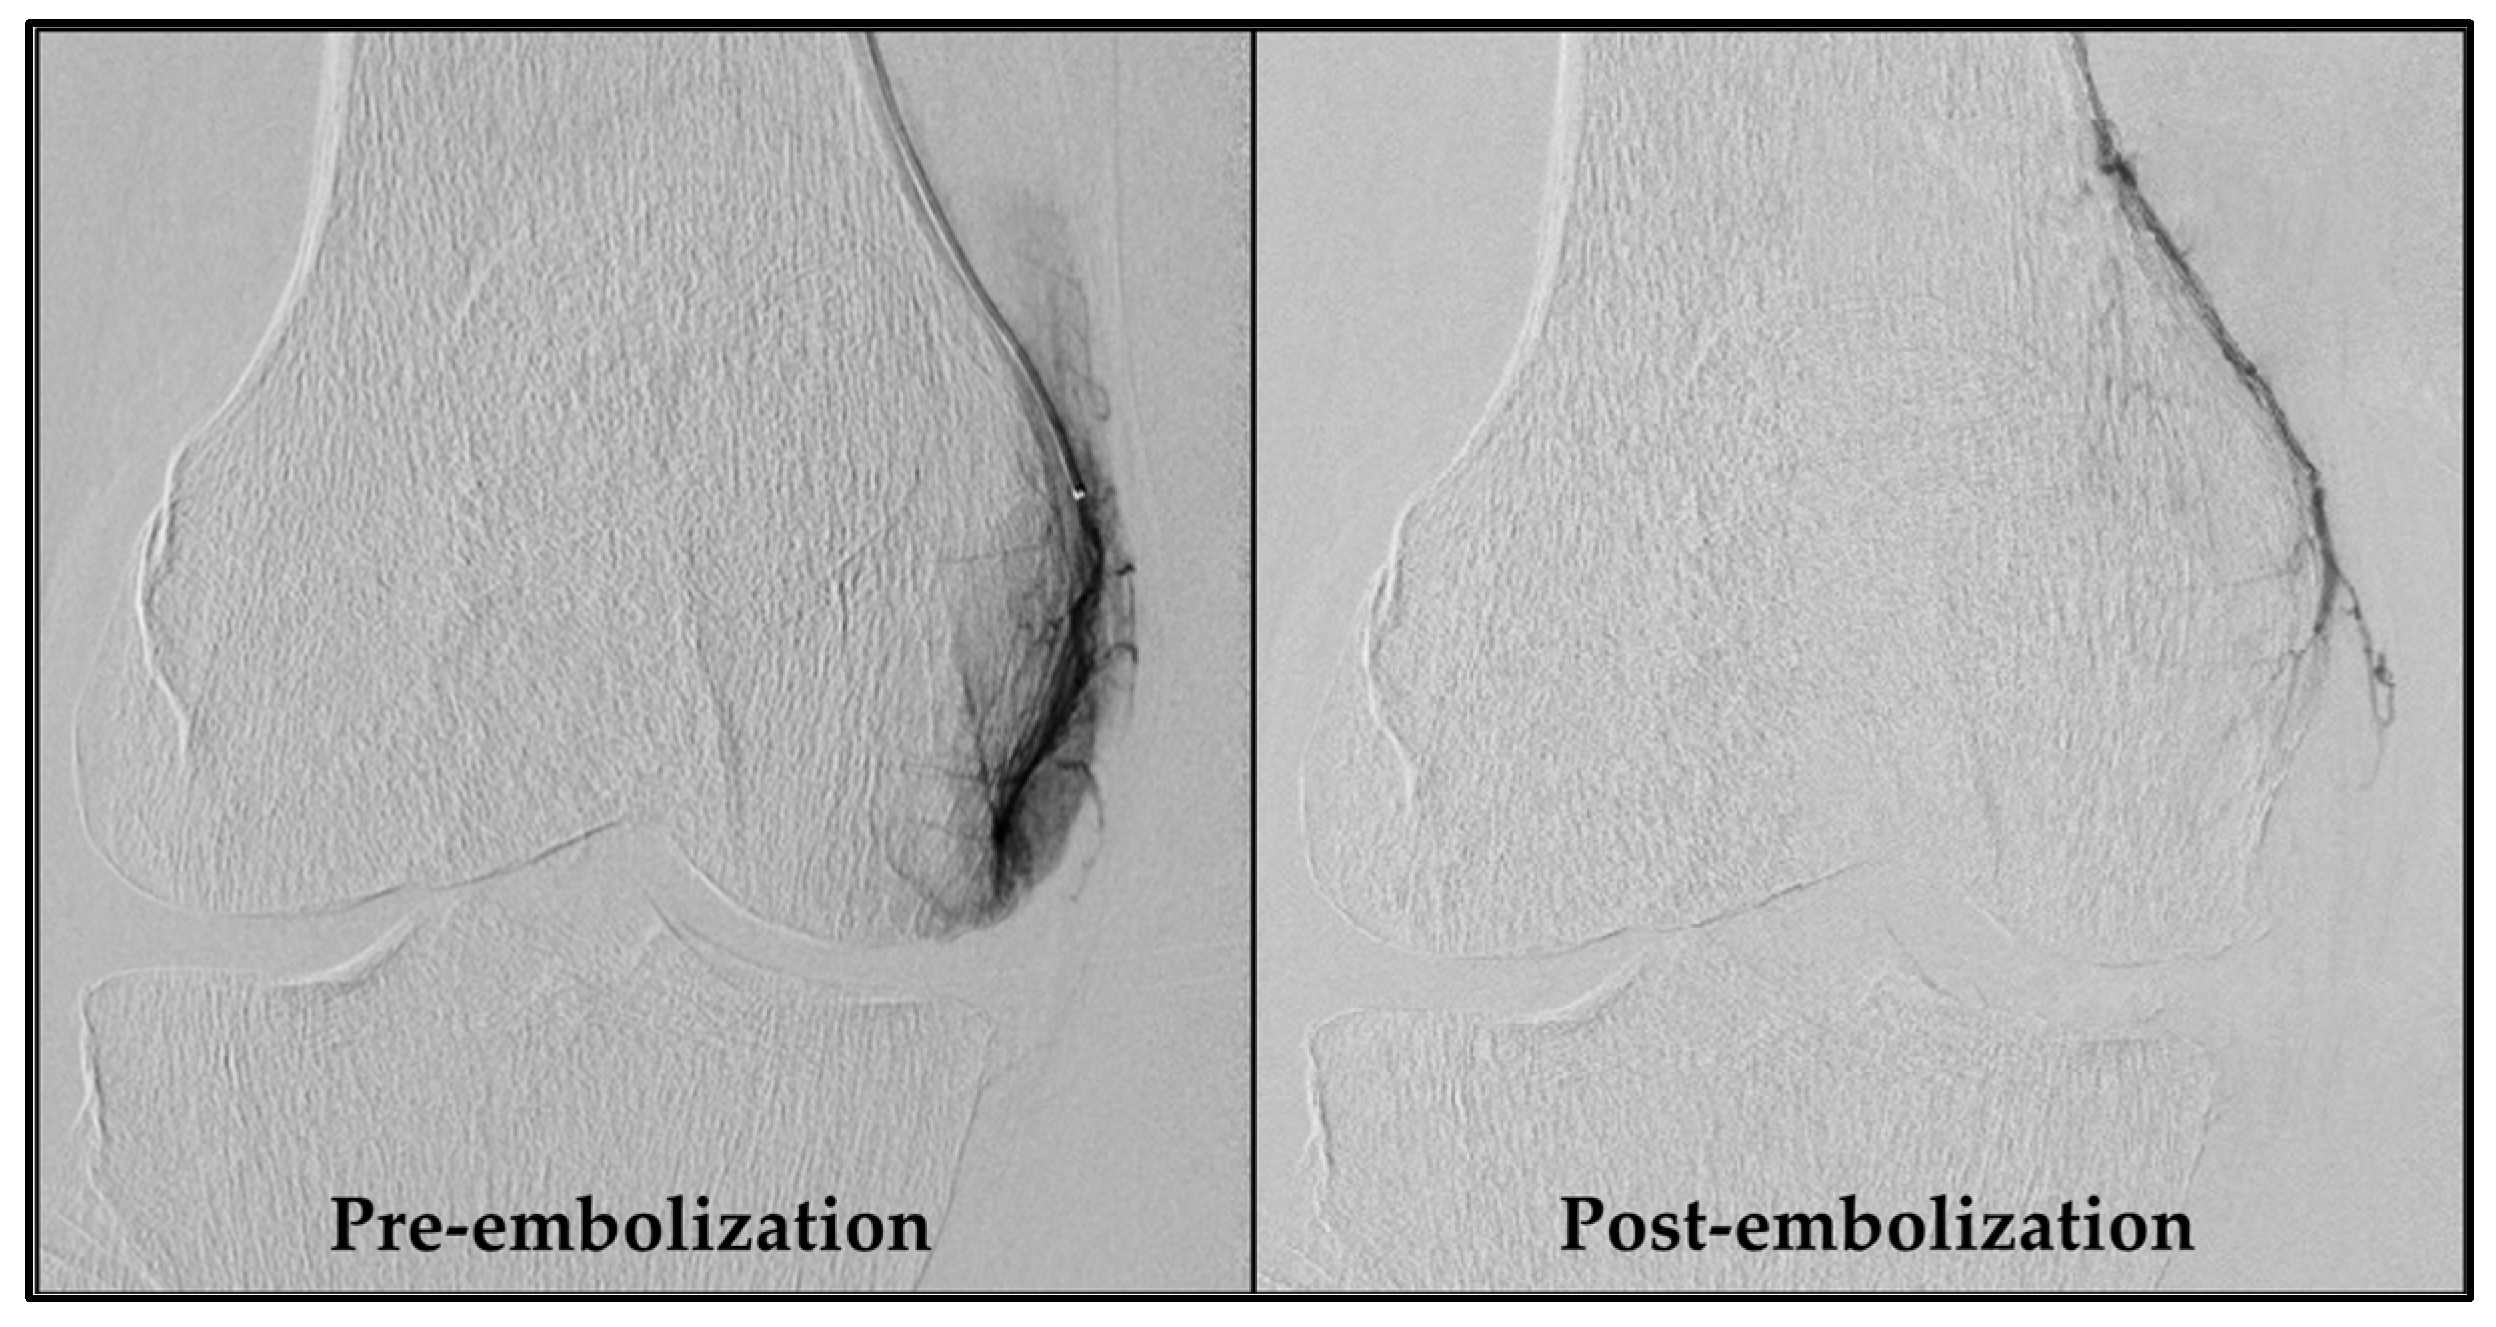

An experienced interventional radiologist (S.H.) performed all GAE procedures, obtaining femoral artery access with a 4-French sheath via the Seldinger technique after administering local anesthesia in the groin. As a standard, access was obtained through the ipsilateral groin and an antegrade approach. If this was not feasible, access via the contralateral groin area was used. Subsequently, a 4-French C2 catheter (Super Torque, Cordis, Miami Lakes, FL, USA) was introduced, and a digital subtraction angiography (DSA) was performed to map the knee’s vascular anatomy. Vessels supplying painful areas of the knee were selectively catheterized with a guidewire (Fathom 14, straight tip, Boston Scientific, Marlborough, MA, USA) and a microcatheter (1.7-French Carnelian, Tokai Medical Products, Kasugai-city, Japan), as described by Little et al. [10]. Nitroglycerin (100 µg/mL) was initially administered, and subsequently when needed, to prevent spasms. Abnormal neovessels were identified by their angiographic blush-like appearance (Figure 2). Ice packs were applied tightly around the knee to minimize non-target skin embolization. Additionally, a cone-beam CT was performed to check for collaterals. Embolization was performed with 100–300 µm Embosphere® Microspheres (Merit Medical, South Jordan, UT, USA) diluted in 20 mL iodinated contrast (Visipaque, 270 mg/mL, GE Healthcare, Chicago, IL, USA), starting with a 0.2 mL particle suspension and adjusted based on feedback until the neovessels were pruned. Hemostasis at the access site was ensured by manual compression and participants rested for four hours before discharge. Technical success was defined as the embolization of at least one target vessel. Procedure time and radiation dose were recorded.

Of the 20 participants referred for GAE, 17 exhibited significant hyperemic blush during pre-embolization DSA and were successfully embolized. In all these cases, the blush was absent in the post-embolization DSA. Two participants showed no significant blush initially, and one patient experienced localized vessel spasm that impeded distal canalization and subsequently hindered embolization. This resulted in a technical success rate of 85% for the procedure.

Figure 2. DSA pre- and post-embolization of the descending genicular artery. The left image shows a distinct blush due to neovessels, formed as a consequence of chronic inflammation. In the right image, these neovessels are pruned by embolization. DSA, digital subtraction angiography.